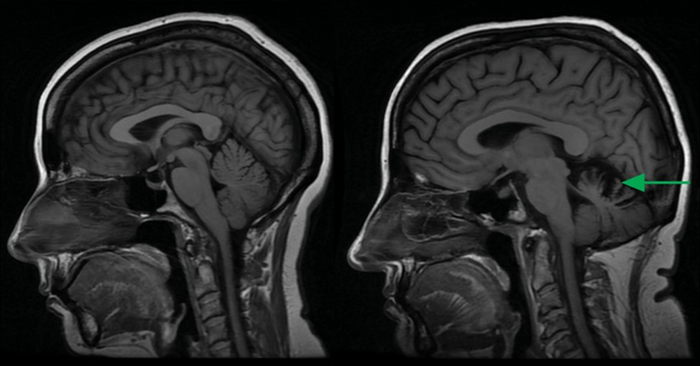

与年龄匹配的健康对照(左)相比,14型脊髓小脑性共济失调患者表现为小脑萎缩(右,绿色箭头)。

图片来源:加州大学圣地亚哥分校健康科学学院